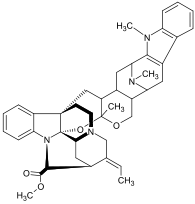

Dimer alkaloids

In addition to the described above monomeric alkaloids, there are also dimeric, and even trimeric and tetrameric alkaloids formed upon condensation of two, three, and four monomeric alkaloids. Dimeric alkaloids are usually formed from monomers of the same type through the following mechanisms:[193]

There are also dimeric alkaloids formed from two distinct monomers, such as the vinca alkaloids vinblastine and vincristine,[27][135] which are formed from the coupling of catharanthine and vindoline.[194][195] The newer semi-synthetic chemotherapeutic agent vinorelbine is used in the treatment of non-small-cell lung cancer.[135][196] It is another derivative dimer of vindoline and catharanthine and is synthesised from anhydrovinblastine,[197] starting either from leurosine[198][199] or the monomers themselves.[135][195]